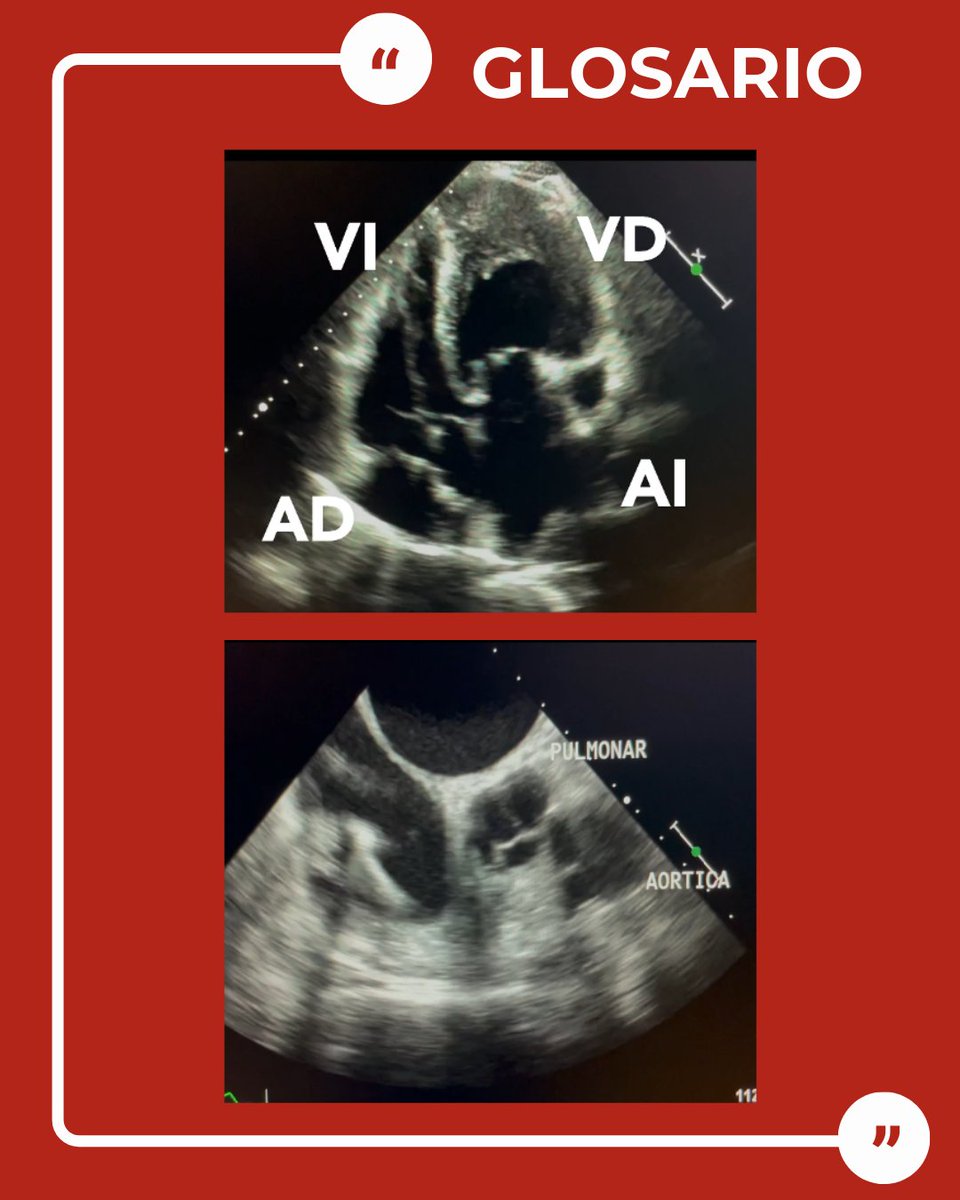

How to Do Echo for Noninvasive Hemodynamic Evaluation of the Patient in the Intensive Care Unit. SIECVI Cardiotweets SONECOM ASARUC SONO Academy asarucpocusacademy SCCM ESICM SEMICYUC #Echofirst #POCUS #CardioTwitter #Cardiology Link (PDF): journals.lww.com/jceg/fulltext/…